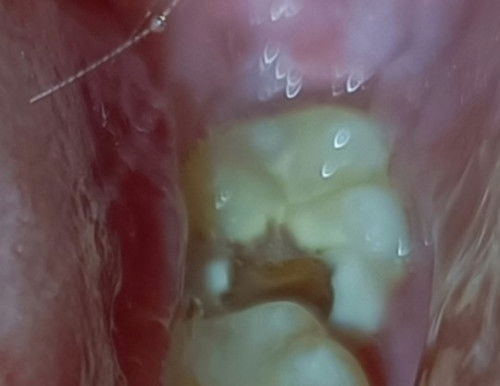

Tooth Extraction

May naka experience na ba nito? Wisdom tooth na kasi nagka tooth decay tapos sobrang sakit nya to the point na nilalagnat nako and di makatulog ng maayos. Naging ganito lang sya nung nagbuntis ako recently kasi 1st weeks ng 1st trimester nakapagpabunot din ako mg ngipin tsaka naka cleaning kasi di ko pa alam na buntis ako nun. Pwede ba tong mabunot? Sobrang sakit kasi talaga. 😭